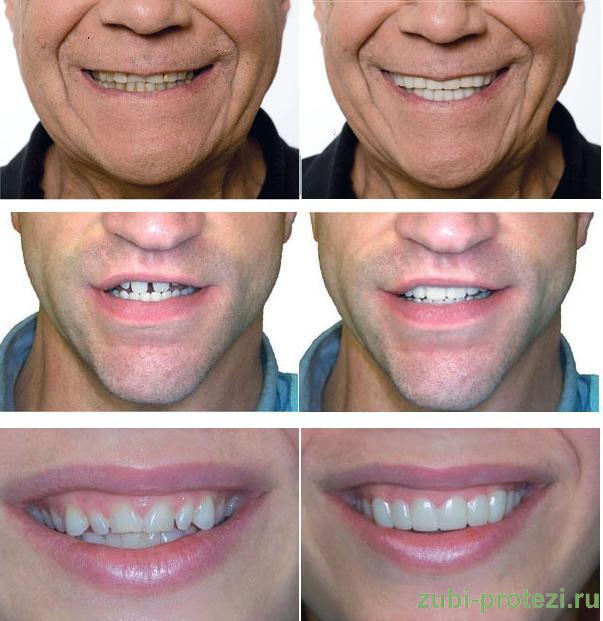

Улыбки в фотографиях: типы и комической моменты

Раздел: Фотогалерея мыслей